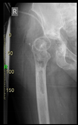

The guiding wire was inserted and controlled with fluoroscopy flashes (Figure 4). The drilling and reaming were carried out in accordance with the recommendations:

Figure 4.

The biocompatible aiming device after insertion of the guiding wire.

The direction of the cup stem was determined by the guide wire. The aiming device was needed to introduce this wire. After removing the aiming device, the next step was the drilling. Since a cannulated drill bit was used, the previously installed wire could guide the process. A self-positioning reaming tool was then used in the drilled channel. In the prepared cavity, the cup was fitted perfectly. Of the two stemmed cups available to us, the McMinn cup (Waldemar Link, Hamburg, Germany) had the simpler geometry and was therefore chosen. The stemmed cup was inserted according to the manufacturer’s recommendation. In the presence of a significant bone defect, a synthetic bone graft may be impacted for substitution.

The radiological examination allowed us to verify the close bone-to-implant contact and the unchanged position of the implant during follow-up.

In all the cases operated with the above-described targeting procedure, the stems of the cups remained between the cortical bone surfaces without perforation of the linea terminalis, as shown by postoperative radiographs. There were no complicated surgical situations. In 16 cases, the wound healings were uneventful, and the hips were able to bear weight again after postoperative rehabilitation.